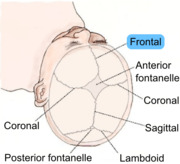

The frontal suture is a fibrous joint that divides the two halves of the frontal bone of the skull in infants and children. Typically, it completely fuses between 3 and 9 months of age, with the two halves of the frontal bone being fused together. It is also called the metopic suture,[1][2] although this term may also refer specifically to a persistent frontal suture[3] (further detailed in section below).

Its presence in a fetal skull, along with other cranial sutures and fontanelles, provides a malleability to the skull that can facilitate movement of the head through the cervical canal and vagina during delivery. The dense connective tissue found between the frontal bones is replaced with bone tissue as the child grows older.

| Human baby skull seen from top. Cranial sutures are depicted. Frontal suture is highlighted in blue. |